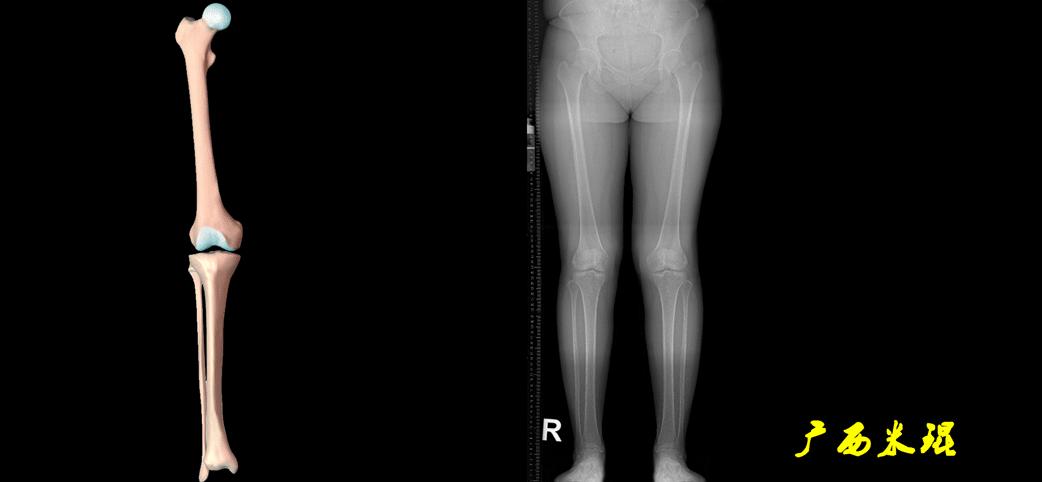

(2)机械轴

机械轴是连接近端和远端关节中心点的直线。

机械轴要分前后位及侧位,站立前后位(也就是冠状面)股骨头中心与踝关节中心的连线通过膝关节中心,这是下肢的机械轴线,也就是下肢力线,常说Mikulicz线。冠状面的力线评估在临床工作中最常用、最基础、最重要。

最常见的下肢畸形发生于冠状面,即膝内外翻畸形,冠状面的对线异常通过应用“对线异常检验”进行分析,机械轴的偏移(MAD)表现为对线异常。

膝内翻是指下肢力线通过膝关节中心点内侧,距中点2mm以上,偏内超过15mm为显著膝内翻。膝外翻是指下肢力线通过膝关节中心点外侧,距中点2mm以上,偏外超过10mm为显著膝外翻。

2、判断畸形的部位

画出下肢全长片中的机械轴和力线轴,确定畸形来自股骨、胫骨还是关节内。首先我们确认股骨机械轴及mLDFA,超出范围为股骨畸形;然后我们确认胫骨机械轴及MPTA,超出范围为胫骨畸形;最后我们确认关节线的汇聚关系JLCA,超出范围为关节内畸形。